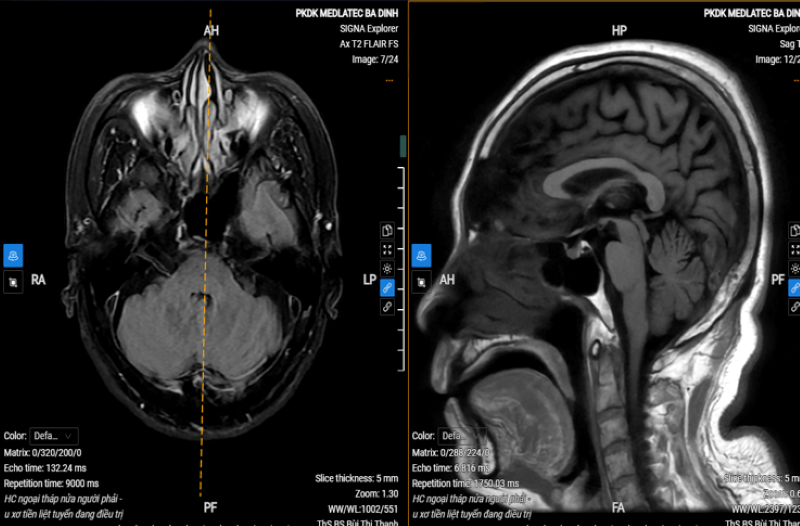

Tại đây, bệnh nhân được thăm khám và chỉ định thực hiện các kỹ thuật cận lâm sàng cần thiết phục vụ chẩn đoán. Đáng chú ý, kết quả chụp MRI sọ não phát hiện hình ảnh thoái hóa myelin chất trắng dưới vỏ bán cầu đại não và quanh não thất hai bên (phân loại Fazekas độ 2), teo não tuổi già.

Kết quả chụp MRI sọ não của bệnh nhân phát hiện bất thường

Dựa trên triệu chứng lâm sàng và kết quả chẩn đoán hình ảnh, chẩn đoán xác định, bác T. mắc Parkinson giai đoạn 1. Bác sĩ kê đơn điều trị ngoại trú và hẹn lịch tái khám nhằm theo dõi tiến triển và điều chỉnh phác đồ.